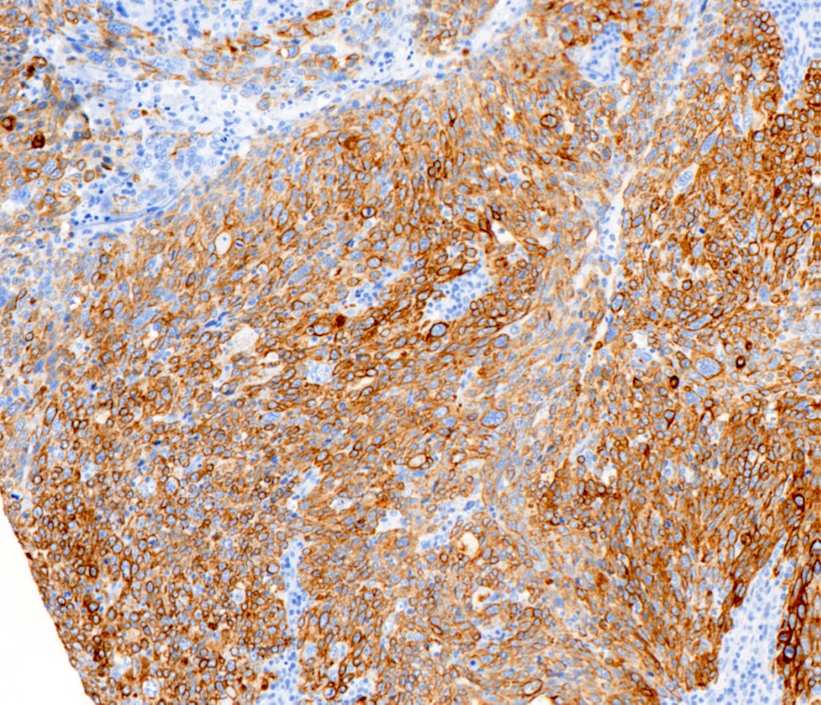

- High molecular weight basal cytokeratins: CK5/6, CK14, CK17 (Clin Cancer Res 2007;13:4429)

- EGFR (J Lab Physicians 2015;7:79)

B. EGFR. Basal-like breast cancers are typically high grade invasive ductal carcinoma of no special type that show solid tumor growth with pushing borders, geographic necrosis, nuclear pleomorphism, a brisk inflammatory infiltrate, a high mitotic index and a high proliferative index with Ki67. Most basal-like breast cancers express basal cytokeratins (keratin 5/6, 14, 17) and EGFR. Answer A is incorrect because while a minor proportion of triple negative breast cancers can express androgen receptor, the prototypical AR positive breast tumor has apocrine features (apocrine carcinoma). Answer C is incorrect because KIT is not characteristically expressed in breast carcinomas. Answer D is incorrect because synaptophysin may be expressed in breast tumors with neuroendocrine differentiation, which typically cluster within the luminal category.